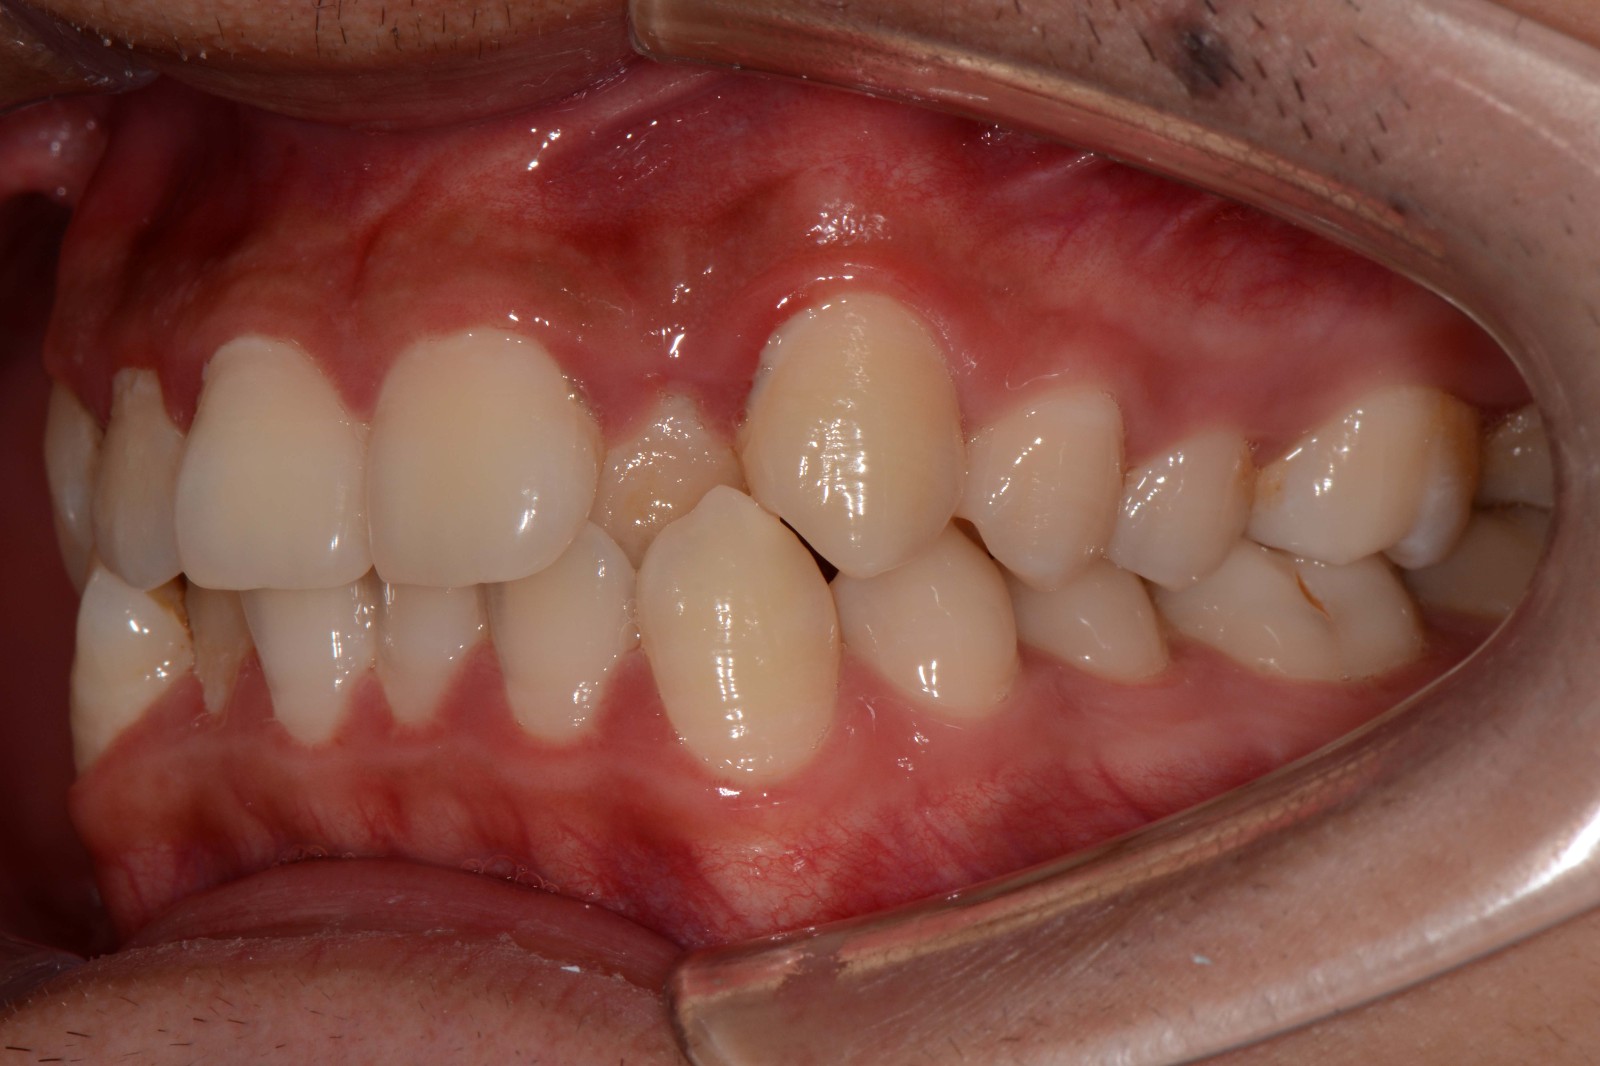

检查:拍摄口内面像照片,拍摄全景片侧位片,口扫,上下颌I-II度拥挤,中线不齐,局部反合,磨牙基本中性关系,上下前牙比较直立。

矫治后: